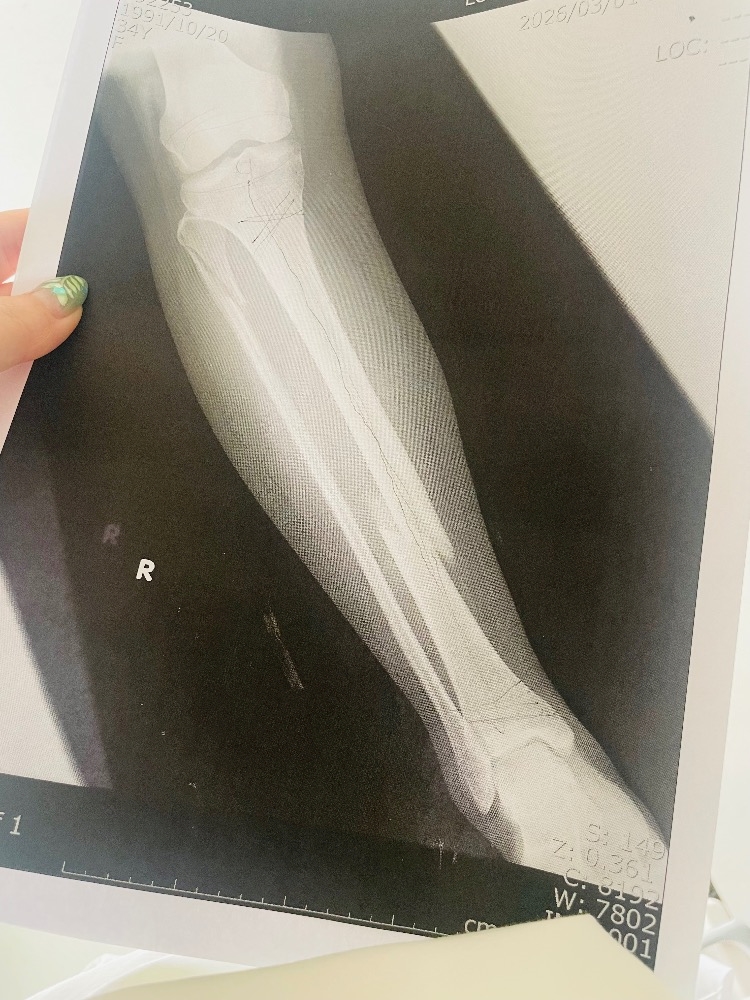

- 超絶お久しぶりです。右足の骨折れてます。まだくっついてません。でも今日から復帰しました‼️偉い、偉すぎる‼️

こんばんは🙋♀️

約1ヶ月の入院生活から

無事帰還しました🙇♀️

まだまだ骨はくっついてませんが

まぁある程度歩けたり

立っていたりはできるので

骨折接客見に来てほしいです🦴🦴

ちなみに3箇所折れてます🙋♀️

ぽっきり😂😂